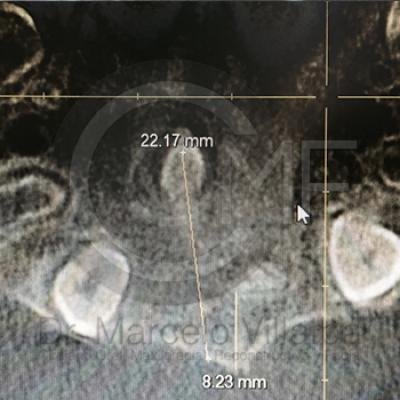

Dientes Supernumerarios